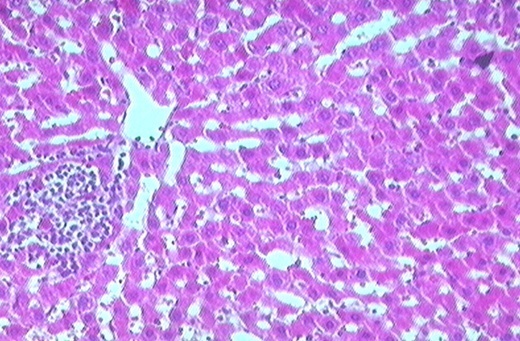

Histological observation of liver tissue of the normal animal (group I) showed a normal liver architecture of hepatocytes since they were well arranged without any alteration at central vein. In (group II) hepatocytes showed severe and diffuse degenerative changes mainly hydropic and fat degeneration.

In addition, focal areas of necrosis and extensive intralobular fibrosis of the two forms porto‐ portal and porto‐central bridging fibrosis were observed.

Fig. 1: (Group I) Photomicrograph of Liver section of a normal control rat.

Fig. 2: (Group II) Photomicrograph of Liver section of CCL4 intoxicated rat.

Fig. 3: (Group III) Photomicrograph of liver section of dose of 250mg/kg.

Fig. 4: (Group IV) Photomicrograph of Liver Section of Dose 500mg/kg.

Fig. 5: (Group V) Photo micrograph of Liver section of Standard group

In (group III) fibrous tissue proliferation was observed around portal tracts along with mild mononuclear cell infiltration mainly lymphocytes. In (group IV) the portal tracts demonstrated moderate infiltration with lymphocytes and few macrophages. Fibrous tissue proliferation around the portal areas and incomplete bridging of the hepatic parenchyma were observed. In (group V) the portal tracts displayed moderate infiltration with lymphocytes in addition to the presence of congested portal blood vessels and hepatic sinusoids